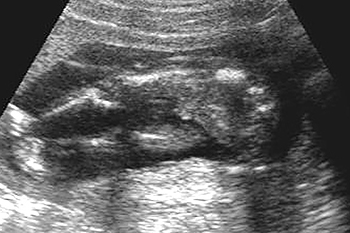

妊娠18週

子宮を横方向に撮影 10週6日

下から縦方向に撮影 10週6日

胎内での窮屈な姿勢は、生まれてからの向きぐせや体のゆがみ、コリにつながりやすくなります。また、膝が伸びた状態が妊娠後期まで続くと、股関節脱臼になりやすいという研究発表もあります。